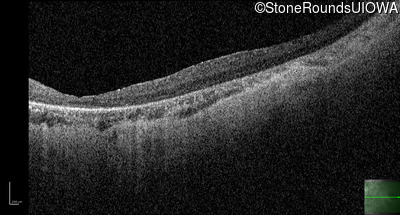

Optical Coherence Tomography - Left - 10/350 sc

Exemplar / OCT Stack